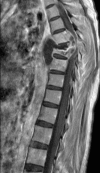

Froin's syndrome associated with spinal tuberculosis